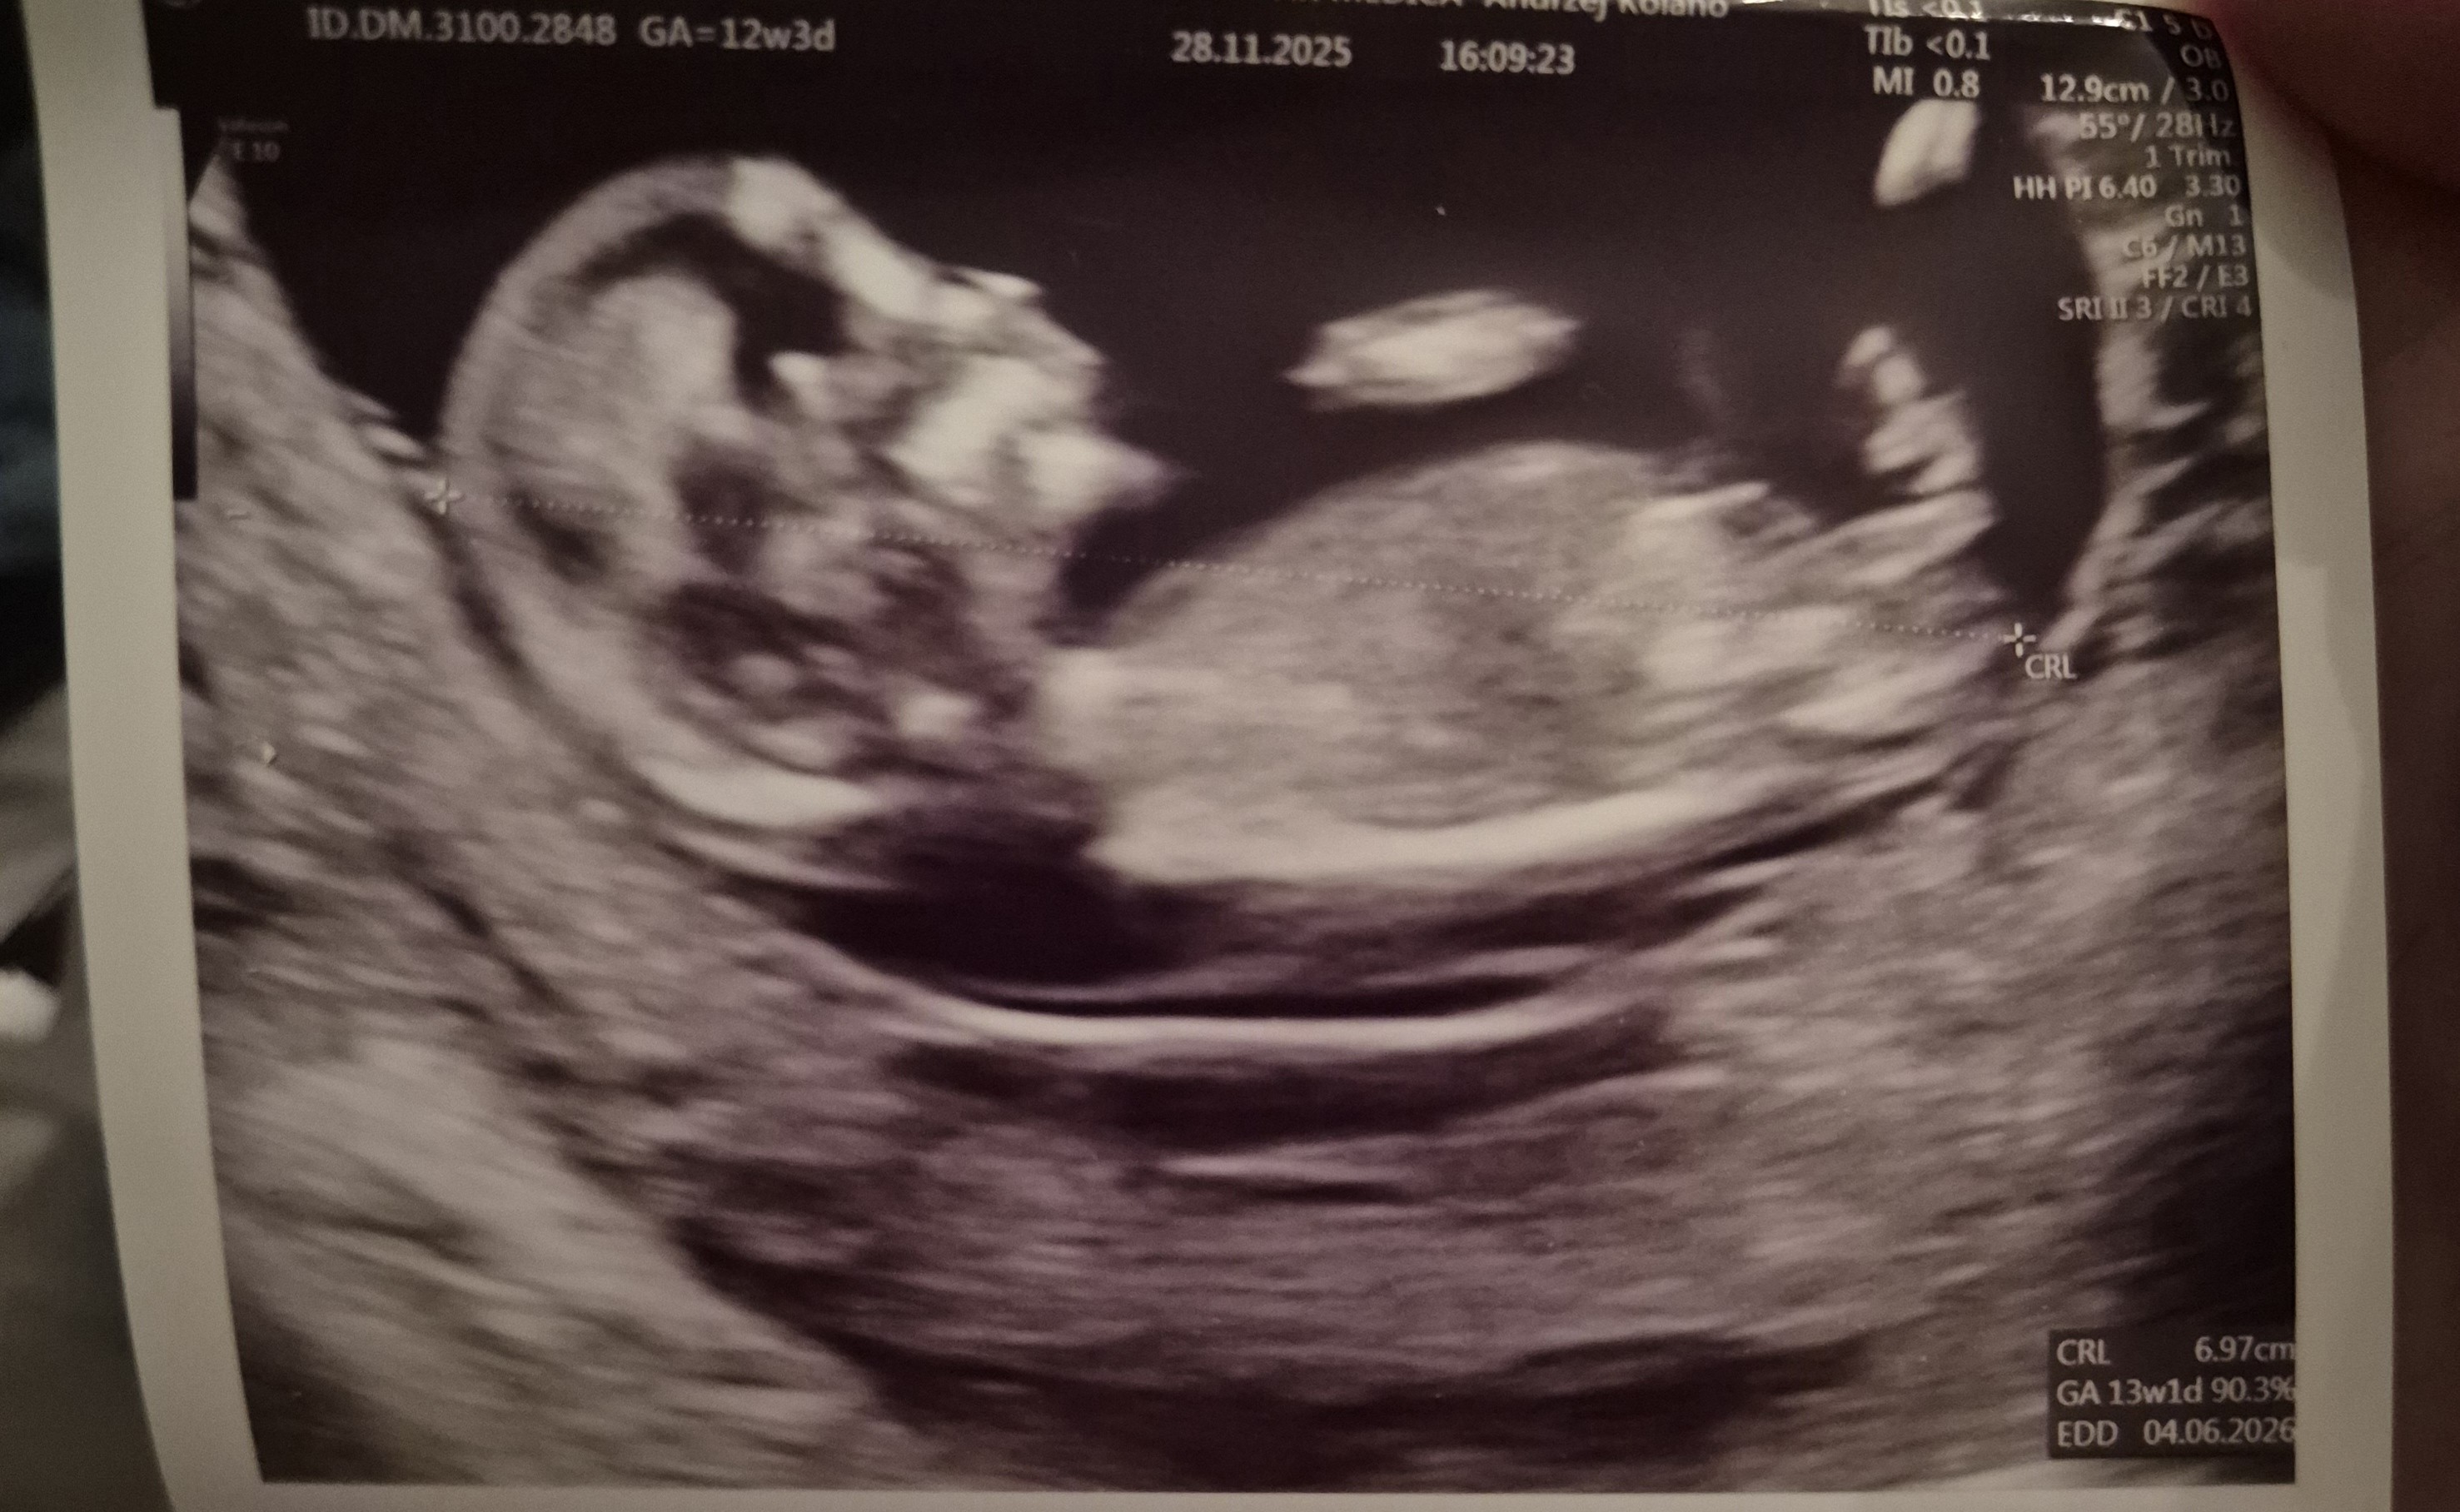

Hej ja też dziś po usg genetycznym. Termin zmieniony na 5 czerwca bo w 9tygodnia termin też taki był i dziś też podobny więc lekarz powiedział że najbardziej prawdopodobny to właśnie 5 a nie 9 czerwca.

Dzidzius podskakiwal

ma prawie 7cm

Lekarz mowi że na chwilę obecną nie widzi nic niepokojącego chociaż mnie niepokoi że przeziernosc 2.50mm no ale to zawsze coś trzeba sobie wkrecac

Nie patrzył co ma miedzy nogami bo mowil że na tym etapie nic nie mówi nikomu